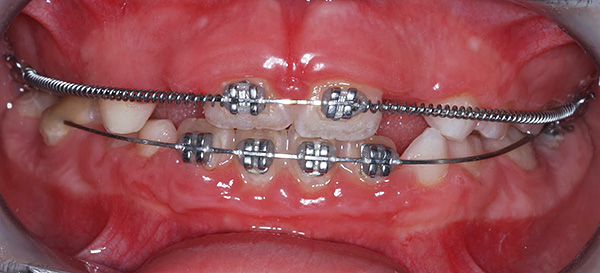

Às vezes, em uma mordida de leite, é necessário usar equipamentos fixos, ou seja, fixar o suporte do sistema ou vários dispositivos de arco de arame em anéis feitos individualmente.

O uso de dispositivos não removíveis é necessário, por exemplo, com malformações congênitas, no caso de rotações e inclinações de dentes que não podem ser fixadas com dispositivos removíveis. E também para a correção da mordida removível, quando a criança usa dispositivos removíveis irregularmente ou se recusa a usar as placas.